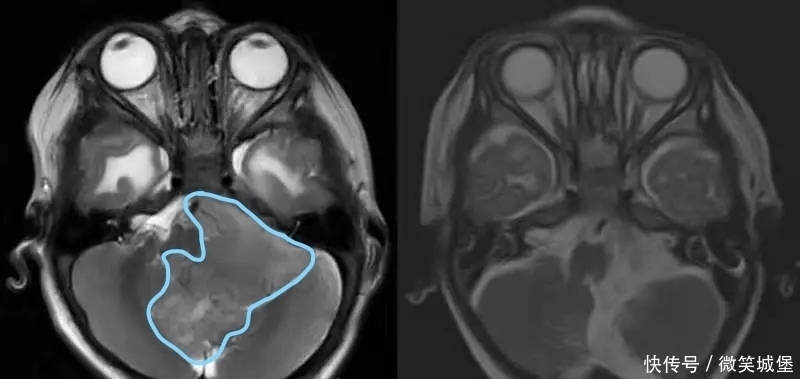

术中可见一个65*54*60mm肿瘤自四脑室正中孔突出,进入枕骨大孔以下,压迫延髓及颈髓。专家在切除肿瘤的同时,注意小心保护相关的神经和血管结构。

文章插图